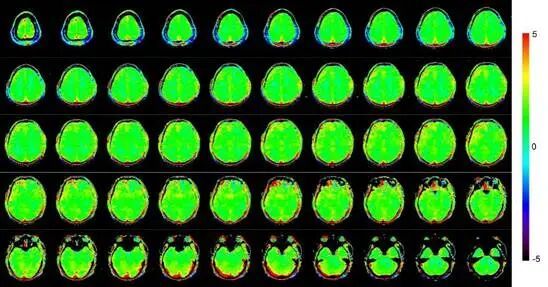

研究团队利用5T超高场磁共振的高信噪比,结合物理信息神经网络(PINN),将动脉自旋标记(ASL)扫描时间从3.5分钟大幅缩短至1分钟(单次采集+4个PLD),同时保持诊断所需的图像质量与定量精度。ASL无需造影剂,对中风、阿尔茨海默病等具有重要价值,但因信噪比低,传统方法需多次采集和多PLD,限制临床应用。新方法峰值信噪比(PSNR)、组内相关系数(ICC)及病灶检测方面均显著优于传统非线性拟合方法,展现出ASL迈向大规模临床应用的巨大潜力。

健康志愿者和中风病人在不同采集时间下使用直接拟合和PINN拟合的脑血流量(CBF)和动脉到达时间(ATT)定量图